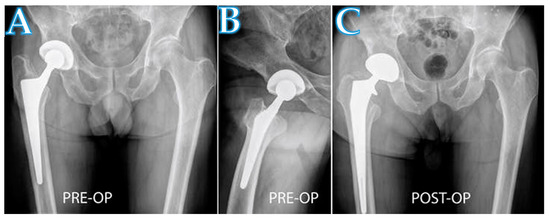

Femoral Revision Total Hip Arthroplasty Performed through the Interval of the Direct Anterior Approach

2.1. Surgical Technique